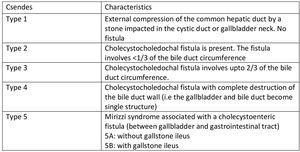

Mirizzi syndrome (MS) is an uncommon disorder brought on by external compression from impacted gallstones in Hartman’s pouch, which obstructs the common bile or common hepatic duct. While Hartman’s pouch is the commonest site of stone impaction, other known sites are the gallbladder neck and cystic duct.1 It is named after Pablo Luis Mirizzi, an Argentinean surgeon who first described it in 1940.1 It is an uncommon complication of chronic cholelithiasis. Mirizzi syndrome is uncommon, with an incidence generally less than 1% among patients with gallstone disease undergoing cholecystectomy, though rates may be higher in specialized centers or populations with longstanding or complicated gallstone disease.1,2 The Csendes classification is the most widely used system for categorizing MS. It describes five types based on the extent of common hepatic duct (CHD) or common bile duct (CBD) involvement by the impacted gallstone, as well as the presence and nature of a cholecystoenteric or cholecystobiliary fistula.2,3 An impacted gallstone causes a pressure ulcer, resulting in external compression of the main duct and eventually eroding into it. This inflammatory phenomenon describes the pathophysiological process leading to MS, at which point the disease may progress to a fistula, with varying degrees of contact between the bile duct and the gallbladder.4 MS poses considerable difficulties in diagnosis and management.

On examination, she was in fair general condition, afebrile and not icteric. The abdominal exam was normal. All relevant laboratory investigations were within normal ranges, and we proceeded with laparoscopic cholecystectomy. Intraoperatively, we noted extensive adhesions involving the gallbladder, omentum, and bowel. The gallbladder was firmly adherent to the cystic plate, rendering the surgery difficult. This prompted the team to opt for a bailout subtotal cholecystectomy. After dividing the gall bladder at the neck, a cholecystoduodenal fistula (Figure 3) less than 5mm was noted along with some bile leaks in the surgical field, reducing visibility. This led to the conversion to an open procedure through a midline incision. The duodenum was primarily repaired and secured with a pedicled omental flap. In an attempt to clearly define the biliary tree anatomy, we decided to explore the CBD. We made a 2cm incision on the anterior aspect of the CBD, which revealed a patent plastic stent in situ and multiple stones. The cystic duct was grossly dilated and found to be in continuity with the CBD. It contained multiple impacted stones, the largest measuring approximately 3cm. All stones were successfully extracted. A bile leak was noted at the cystic stump and was repaired primarily. The CHD was almost collapsed. The presence of a cholecystoenteric (cholecystoduodenal) fistula in a context of MS without gallstone ileus made us classify this as a Type 5A according to Csendes classification (Figure 4). The CBD was then repaired primarily. Abdominal irrigation was done, and a drain was left in situ. Postoperative monitoring was negative for bile leaks. The patient improved clinically, with liver function test normalising and was discharged after 10 days. Clinic follow-ups were scheduled every 3 months. The patient remained asymptomatic and is currently doing well and improving.